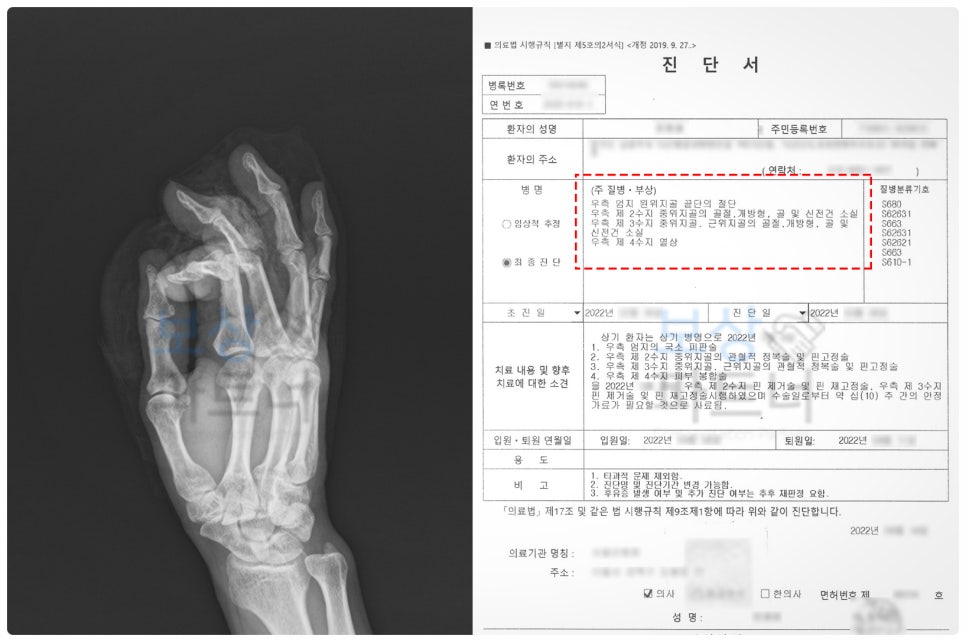

50대 재해자께서는 건축 목공 업무 중, 톱날에 손가락을 크게 다치는 부상을 당하셨습니다.

이 사고로 엄지, 검지, 중지 세 손가락에 걸쳐서 절단, 골절, 힘줄 파열이 발생하였는데요. 엄지의 절단된 부위를 덮기 위해 **피부조직 이식 및 재건술(국소 피판술)**이 이루어졌습니다.

그리고 검지와 중지는 골절 부위를 절개하여 직접 눈으로 보고 뼈를 정렬한 뒤, 금속 핀으로 뼈가 정상 위치에 유합되도록 도와주는 핀고정술을 진행하였습니다. 이러한 과정은 고난도 수술로서, 꼭 수지 전문 병원에서 시행할 필요가 있습니다.

① 올바른 후유장해 진단서 발급

전문의가 발급하는 진단서는 보상금 산정 시 중요한 역할을 하는데요. 하지만 실무적으로는 주치의로부터 제대로 된 장해평가를 받기는 쉽지가 않습니다. 그러므로 섣불리 서류를 발급받을 것이 아니라, 객관적인 평가를 받을 수 있는 곳을 신중하게 알아보는 것이 필요합니다.